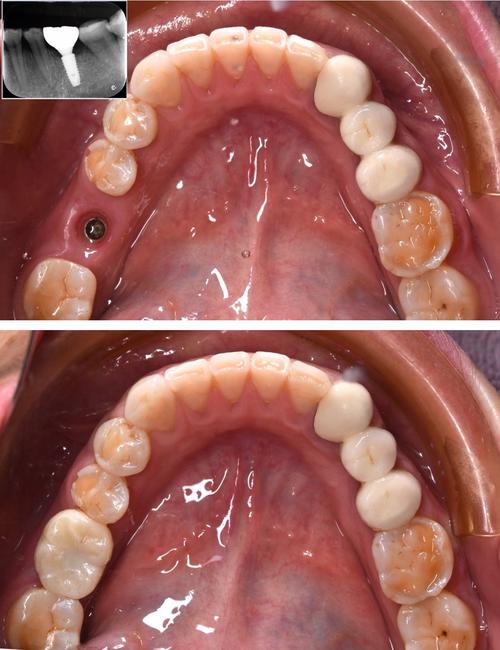

- 了解经验: 从业年限、主攻方向、年种植量、成功案例(可以要求看类似病例的术前术后照片,注意保护隐私)。